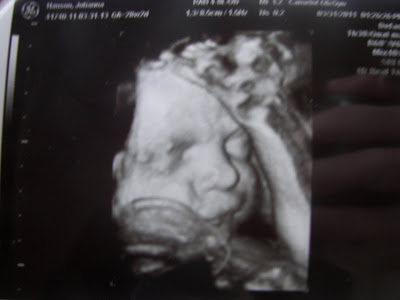

Yesterday, I had an ultrasound and we got some amazing pictures of our little guy. I'm seriously smitten. He is so stinkin' cute!

Yep! Those are his feet up on his head. Completely breech right now. He's got a few weeks to turn. Let's hope he does:)

And, yes, I do realize that most of the rest of the world won't think these are as cute as his Mommy does, but I had to post them. We have never gotten these kind of u/s pictures with our other children and I am loving it! I just stare at the picture and marvel that that little face is inside me right now. Wow, wow, and wow! Thank you, God, for the amazing gift of life!